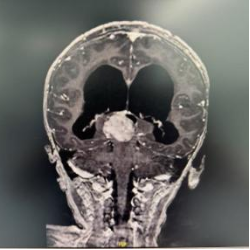

患者女,4岁6月,症状为双上肢震颤、右侧踝阵挛。院外头颅MRI平扫示松果体区占位性病变并梗阻性积水、间质性脑水肿。在上海儿童医学中心张江院区神经外科进一步行头颅MRI平扫+增强检查,于松果体区见团块样占位,大小约29.4*26.7*26.5mm,T1WI低信号,T2WI稍高信号,有明显不均匀强化。影像学诊断为右侧丘脑至松果体区占位,考虑恶性肿瘤。

患儿术前MRI图像